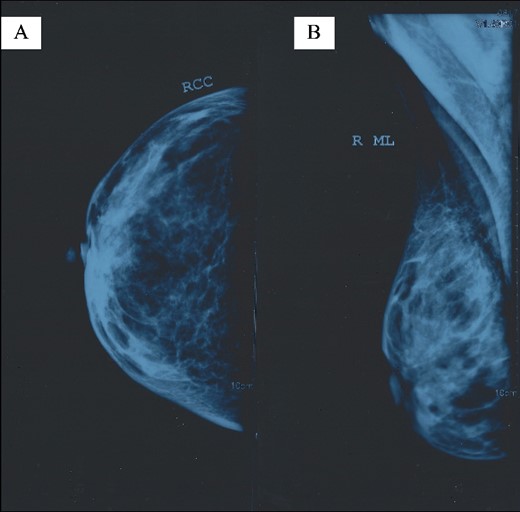

Mammograms were obtained, but they did not report any pathological findings (Fig. 1). Right breast ultrasound (US) reported fibrocystic disease and a cystic mass of 9.5 mm in diameter located at 11 o’clock, which was larger than the rest of the existing cysts (Fig. 2). Breast elastography reported oedema, diffuse thickening of the skin, and an increase in the vasculature of the upper medial quadrant of the right breast. No cystic or solid mass was reported. Additionally, an enlarged lymph node, 21 × 6 mm in size, was reported to be located in the right axilla. This lymph node had an echogenic medulla and an enlarged cortex.

Right breast mammogram without pathological findings: (A) right craniocaudal (RCC) view and (B) right mediolateral (ML) view.